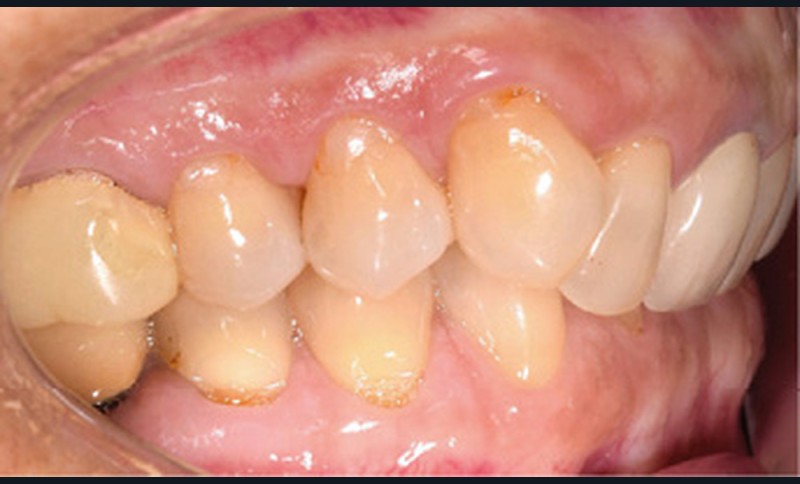

Examen endobuccal (fig. 2a-e)

L’arcade maxillaire est asymétrique et parabolique. Elle présente une mésio-position du secteur 1. On note des rotations mésio-vestibulaire de 13 et disto-vestibulaire de 23 et une palato-version incisive. Les restaurations prothétiques sur 11, 16 et 24 semblent à refaire. L’arcade mandibulaire est asymétrique et parabolique avec une couronne sur implant en 36.

Dans la dimension transversale, on constate une endoalvéolie maxillaire. Dans la dimension sagittale, on observe une classe II plus importante à droite où elle est complète de 5 mm. Le surplomb est absent et la supraclusion totale (6 mm) par supra-alvéolie mandibulaire.